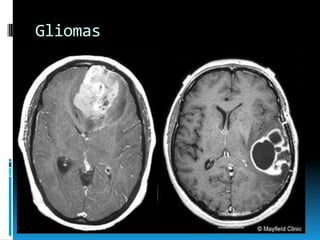

Gliomas

 Astrocitomas,

oligodendrogliomas,

ependimomas.

 Cuadro clínico: anatómico-dependiente.

Gliomas  Astrocitomas, oligodendrogliomas, ependimomas.  Cuadroclínico: anatómico-dependiente.  Ependimoma  Hidrocefalia 2aria obstrucción de 4to ventrículo.